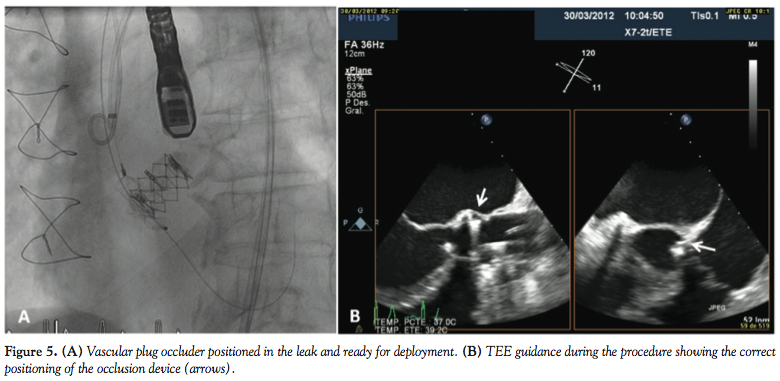

Four days after diagnosis, under general anesthesia and TEE monitoring, percutaneous closure was attempted. Using an 8 Fr sheath through the right femoral approach, we were able to advance a straight-tip 0.035˝ Terumo guidewire, probing the defect. Subsequently, a 4 Fr multipurpose catheter (Cordis) was advanced into the LV and the wire was exchanged by an Amplatz Extra-Stiff guidewire in order to advance the plug delivery system. An 8 Fr Amplatzer TorqVue sheath was placed through the defect in the LV and a 12 x 5 mm Vascular Plug III was delivered in the defect (Figure 5A) with practically total disappearance of regurgitation. TEE monitoring confirmed the correct positioning of the occluder device (Figure 5B).